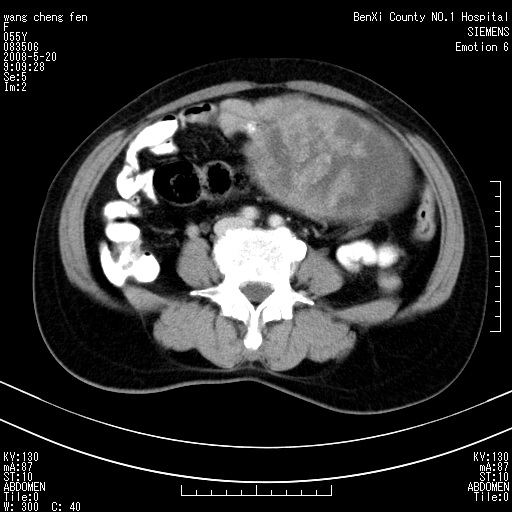

左侧附件区巨大囊实性病灶,边缘光整,病灶囊壁较厚,增强示囊壁及实性部分明显强化,强化呈度与宫体实质大致相同,宫腔积液征像,未见盆腔积液等其他异常,考虑左侧卵巢囊腺癌,不除外囊腺瘤及浆膜下肌瘤坏死

左侧附件区巨大囊实性病灶,边缘光整,病灶囊壁较厚,增强示囊壁及实性部分明显强化,强化呈度与宫体实质大致相同,宫腔积液征像,未见盆腔积液等其他异常。绝经后阴道流血3个月,结合病史左侧卵巢囊腺癌首先考虑,宫腔扩大不除外累及。期待结果。

缺延时片子,左侧盆腔囊实性占位,来自于左侧附件可能性大,囊腺癌可能性大。

囊实性肿块分隔厚度较大,厚薄不均,增强实性成分明显强化,有不规则阴道流血,卵巢囊腺癌可能性大。